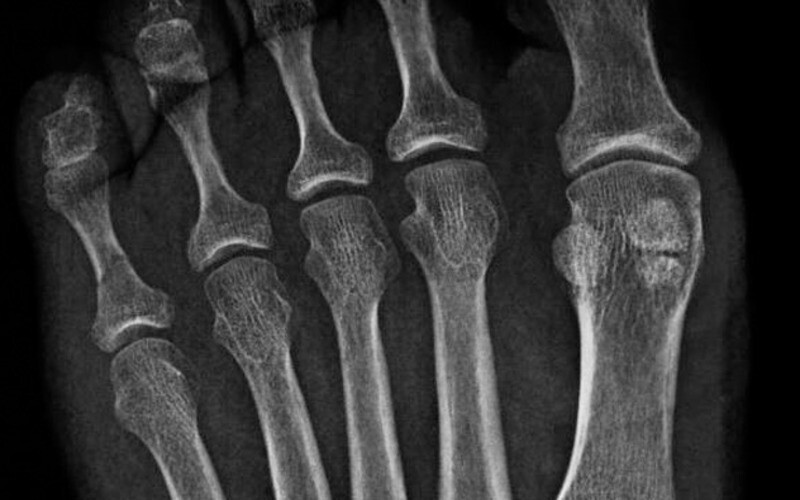

«Шестые» пальцы

Каким образом пандам удается удерживать стебли бамбука? Конечно, благодаря противопоставленному большому пальцу. Правда, на самом деле это не полноценный палец, как у человека, а вырост из пястной кости. Но функция ведь сходна.